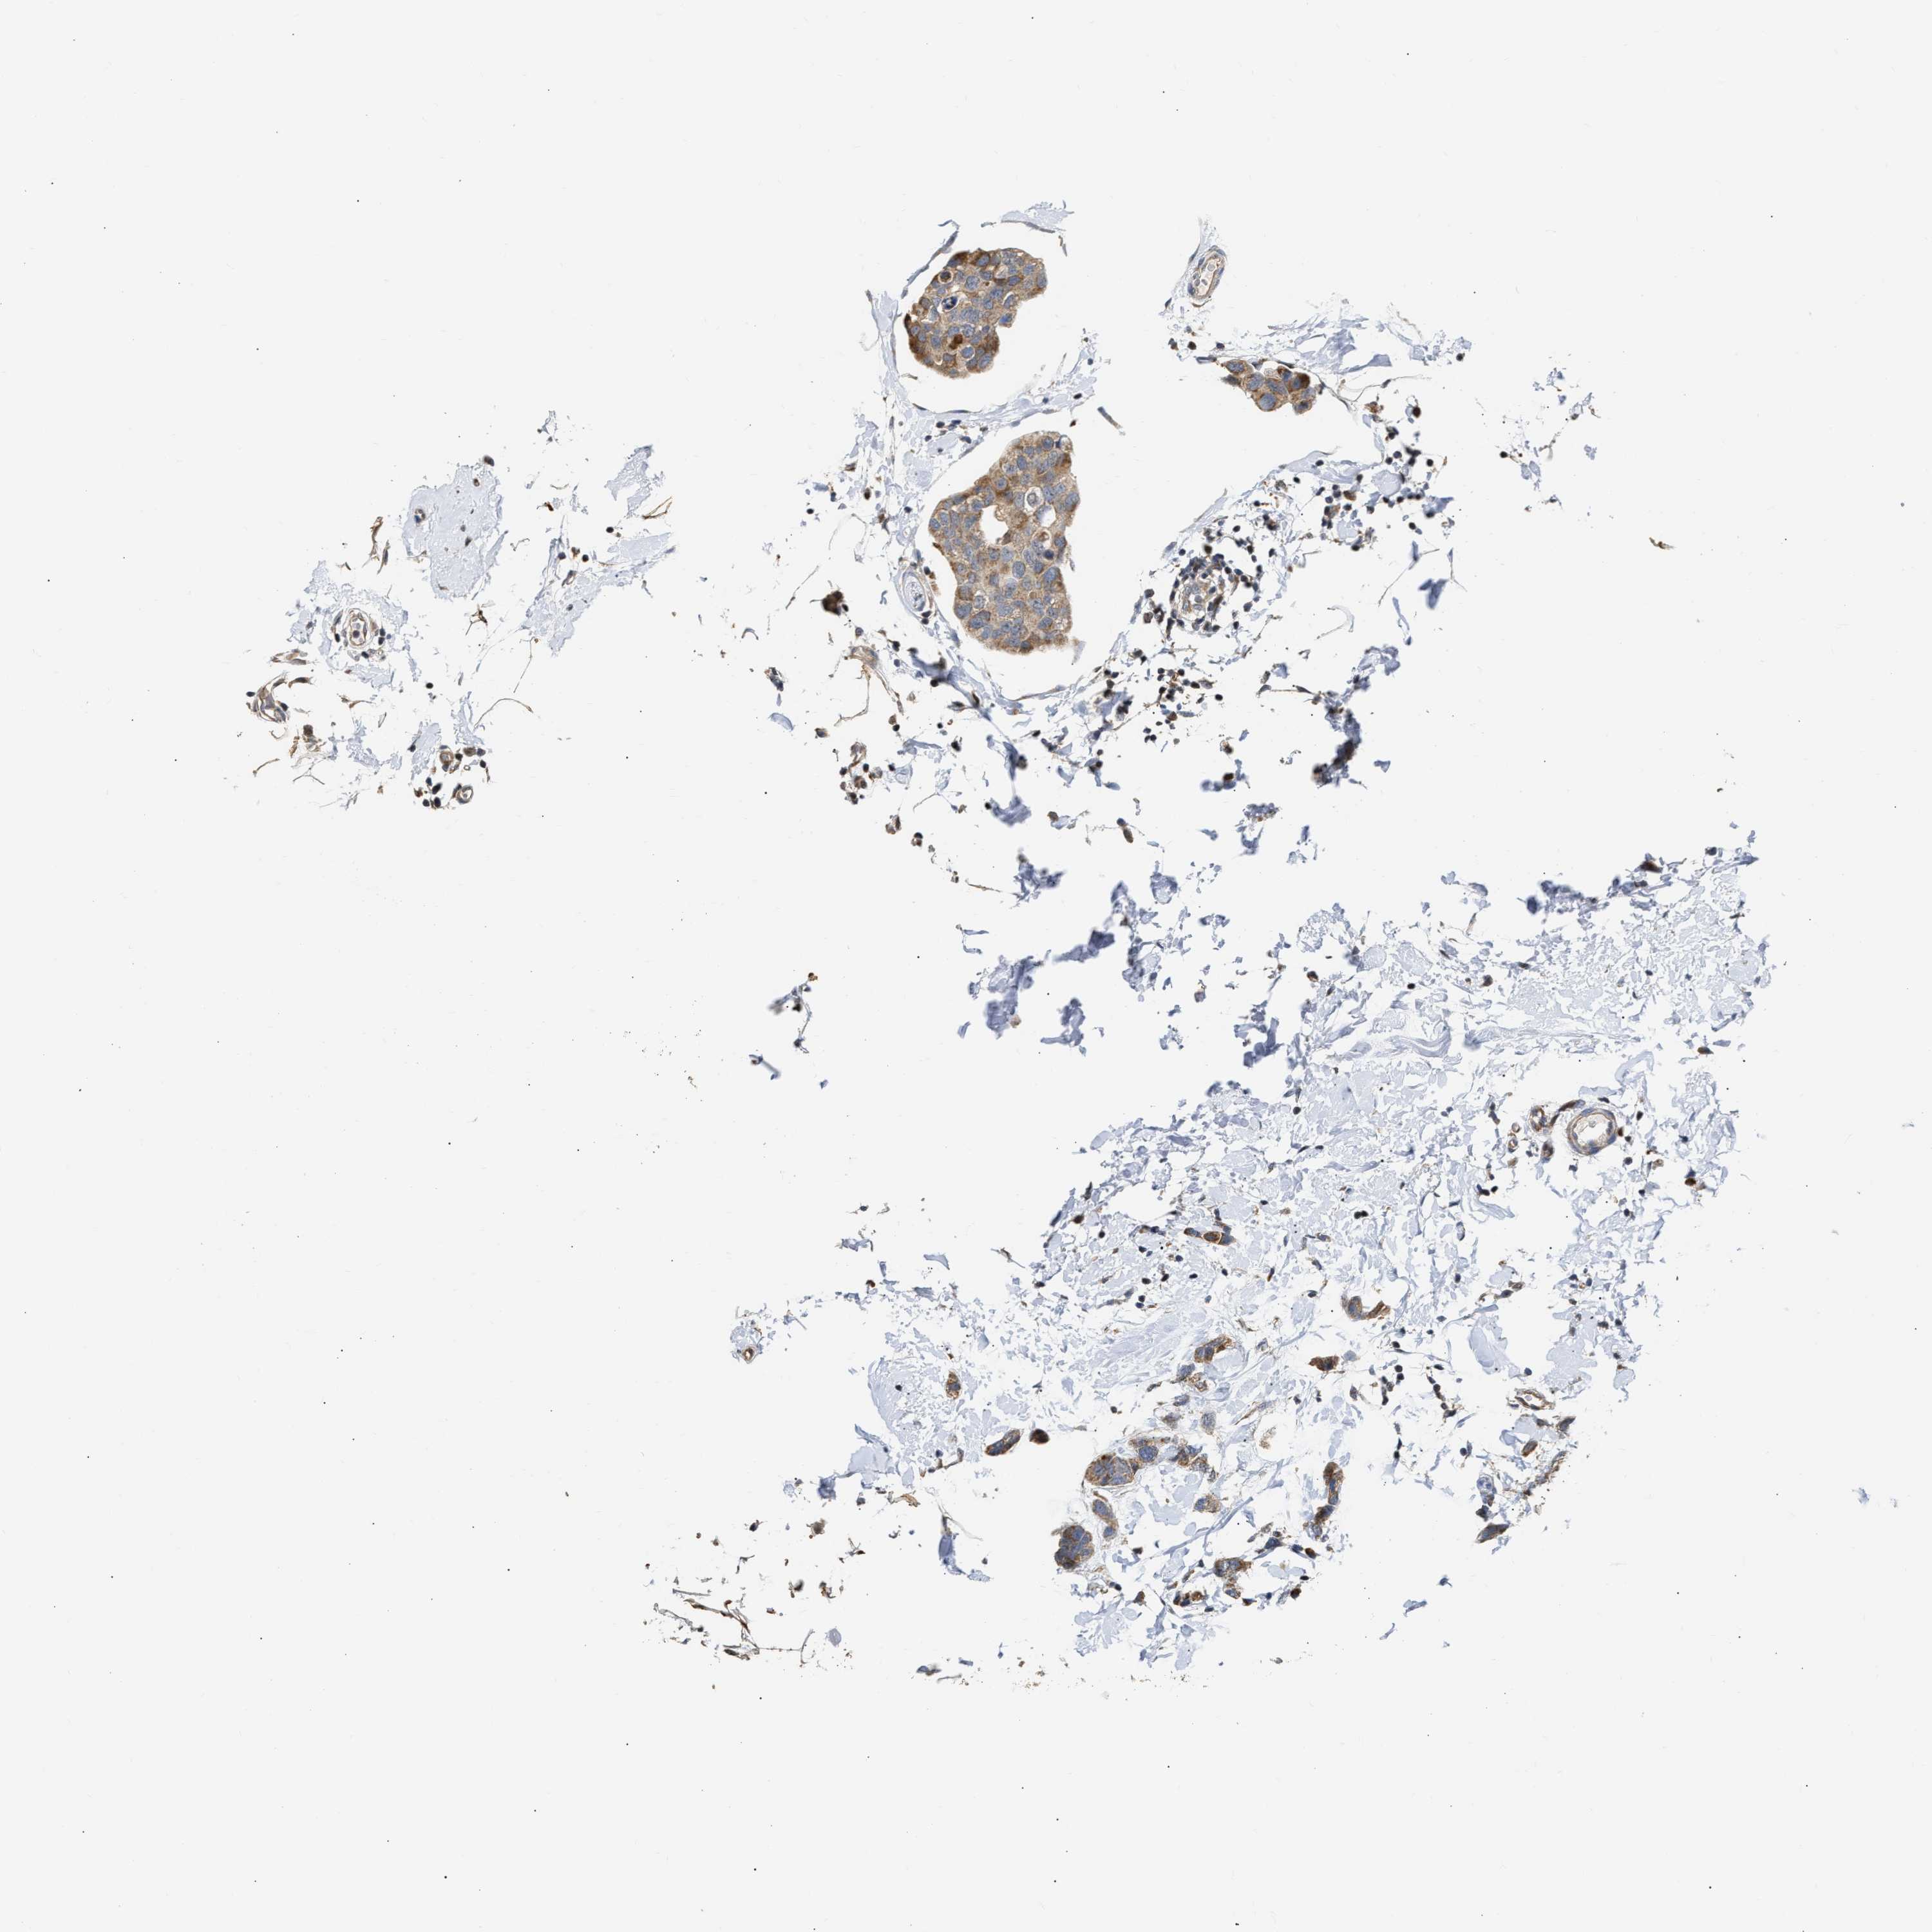

CANCER BREAST CANCER Show tissue menu

BRCA TCGA BRCA VALIDATION PROTEIN EXPRESSION